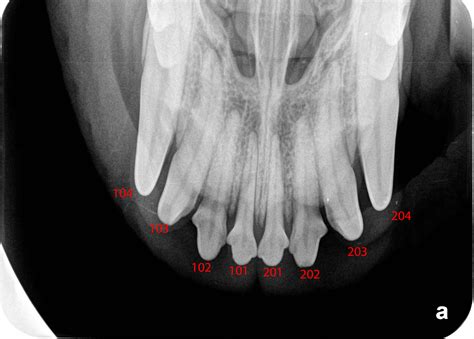

Normal Canine Dental Radiographs - Vet Dent Edu

TitleNormal Canine Dental Radiographs - Vet Dent Edu